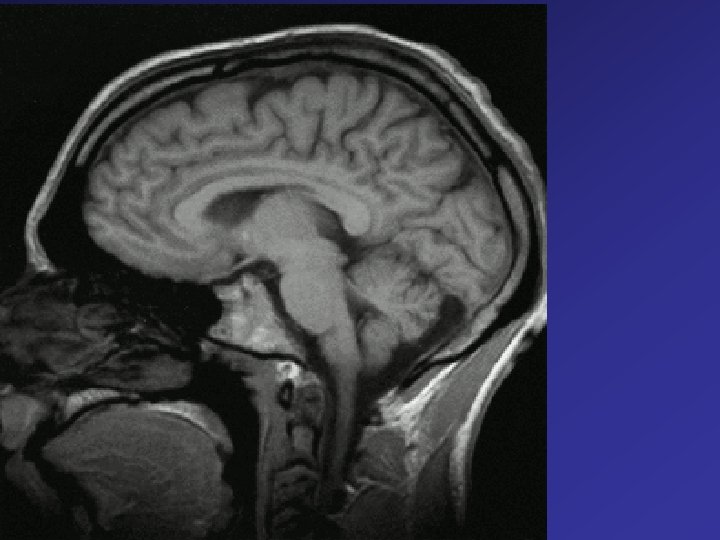

Woskowe modele anatomiczne

Anatomia jako nauka zajmuje się poznawaniem budowy ludzkiego ciała. Nazwa anatomii pochodzi od greckiego słowa „ anatamnein”, które oznacza rozcinać, rozczłonkowywać, gdyż na tym polega najstarsza metoda badania w tej nauce. Obecnie mamy wiele innych metod diagnostycznych prowadzących do poznania budowy ludzkiego ciała: Ultrasonografia RTG Tomografia komputerowa Spiralna tomografia komputerowa Jądrowy rezonans magnetyczny Metody te pozwalają na wydzielenie poszczególnych części ludzkiego ciała jakimi są narządy, układy narządów, tworzące organizm czyli ustrój.